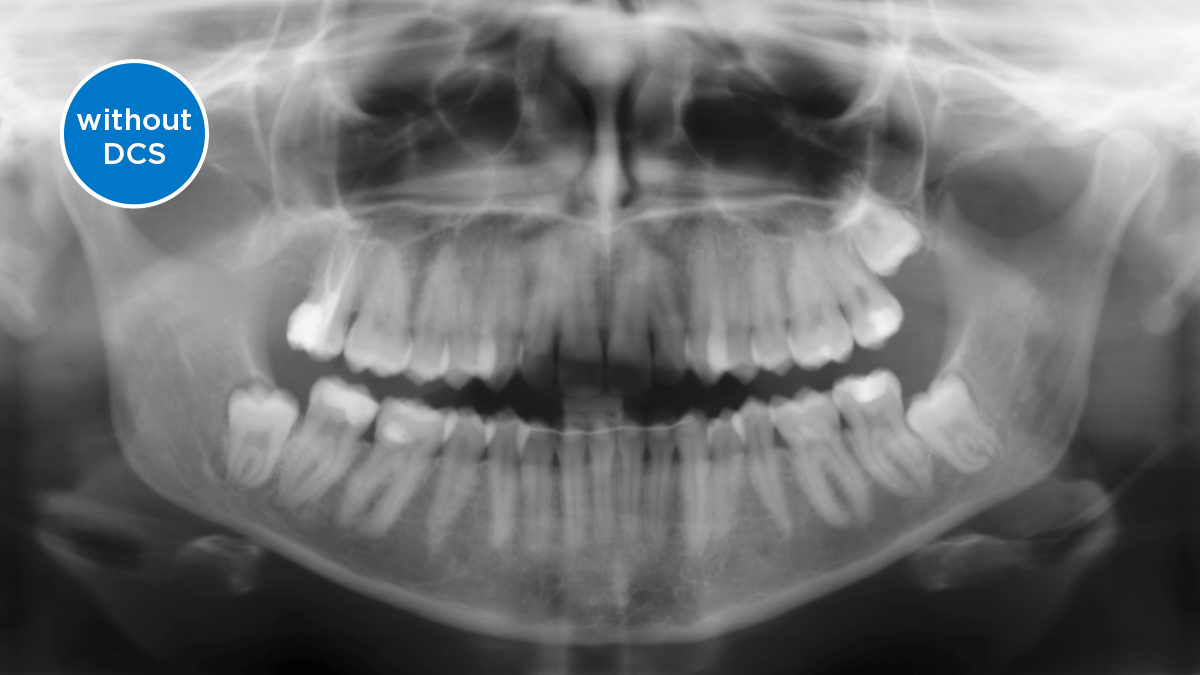

El sensor de conversión directa (Direct Conversion Sensor, DCS) ha revolucionado el estándar de la imagen panorámica. Las imágenes radiológicas se convierten directamente en señales eléctricas. Por lo tanto, no hay pérdida de señal debido a conversión de la luz, como es el caso de los sistemas convencionales. El resultado: imágenes con un alto nivel de nitidez y contraste, incluso con una dosis de radiación extremadamente baja. Para obtener información de diagnóstico precisa a fin de apoyar el tratamiento objetivo.

La imagen a continuación muestra una radiografía panorámica con y sin tecnología DCS. Usando la flecha, arrastre el control a través de la imagen para ver la diferencia que el sensor de conversión directa hace con la calidad de la imagen y las posibilidades de diagnóstico.